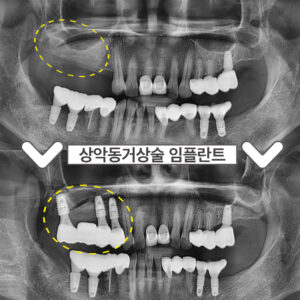

부천시청역치과 임플란트 뼈 이식이 필요하다면? 안녕하세요 😀 이로운 치료를 선사하는 서울이로운 치과입니다. ^^ 임플란트를 하고 싶어도 잇몸뼈가 충분하지 않아서 동네병원에서 하지 못하는 경우가 종종 발생하는데요. 오늘은 잇몸뼈가 없어서 임플란트를 할 수 있을지 고민하시는 분들을 위해 ‘뼈가 없어서 임플란트 치료가 가능한지 모르겠다며’ 본원을 찾아주셨던분의 케이스에 대해 설명드리려 합니다. 🙂 처음 본.원을 더보기…